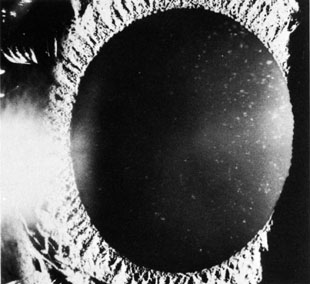

Although the advent of laser iridotomy has greatly decreased the incidence of cataract development compared to surgical iridotomy, laser iridotomy (Fig. 4) also can cause lenticular changes. Several reports have demonstrated small lens opacities appearing at the site of the laser beam after laser iridotomy (Fig. 5),36,41,42 but no progression of these opacities has been described. Zonular rupture can occur from the laser as well.43 One case report describes an “exploding” cataract with posterior capsular rupture and release of cortical material into the vitreous following a YAG laser peripheral iridectomy.37

Fig. 4. Laser iridotomy. Black arrow points to iridotomy; white arrow indicates lens opacity.

Fig. 5. Transient lens opacity at site of laser iridotomy (arrow) (disappeared within 2 weeks).